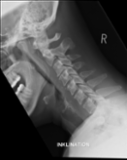

Acute calcific deposit on the enthesis of the longus colli muscle

The severe cervical spine pain prompted an emergency MRI examination, which showed a clear prevertebral inflammatory soft tissue process. On close inspection, a calcific deposit anterior to the dens axis can already be suspected on MRI (especially T2 or axial T1fs Gd+). The calcium depot is only shown very fluffy on X-ray and CT, suggesting an acute stage with precipitation/resorption of the calcific milk.